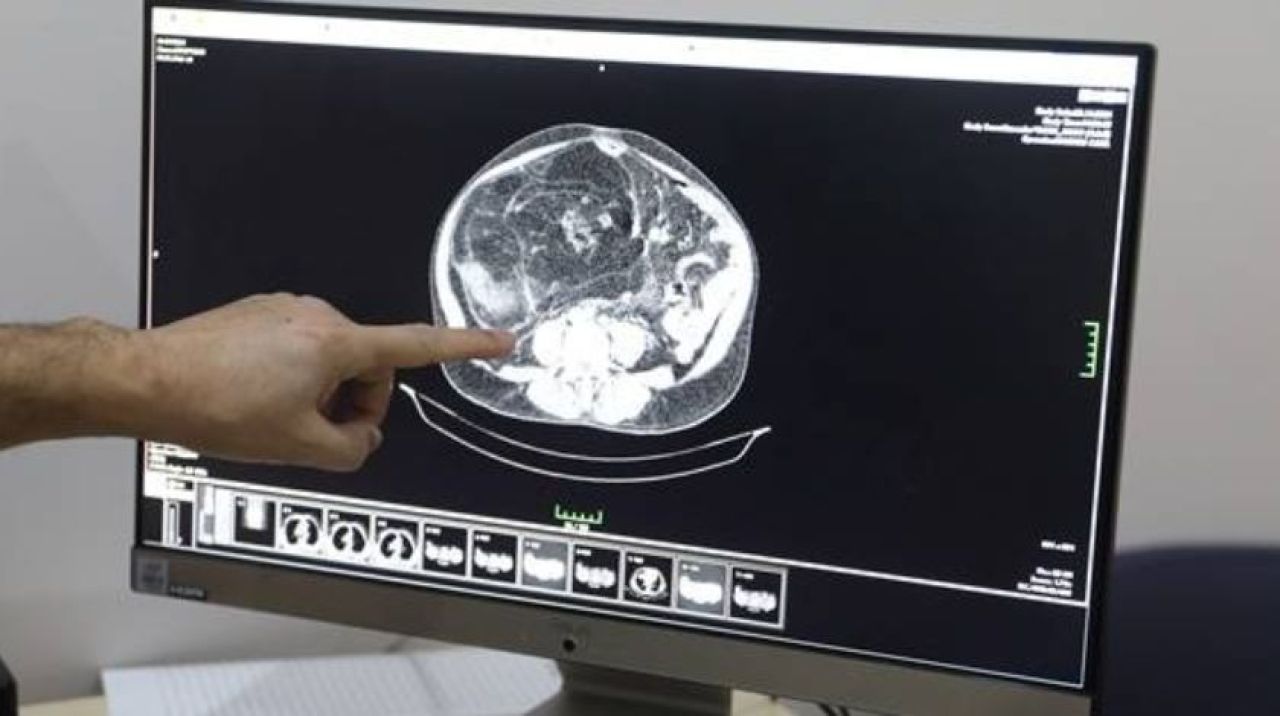

Karın ağrısı ve nefes darlığı şikayetiyle Yüzüncü Yıl Üniversitesi Dursun Odabaş Tıp Merkezine başvuran Çiftçi'nin tetkiklerinde karnında kitle tespit edildi.

Bunun üzerine ameliyata alınan Çiftçi'nin karnındaki 35 kilogramlık kitle 5 saatlik operasyonla alındı.

"Hasta uzun süre karnında şişlik hissediyormuş. Yaptığımız tetkiklerde 35 santimetre büyüklüğünde kitle saptadık. Bu, hekimlik süresince rastladığım ender vakalardan biri. Yüz binde birkaç kişide ancak rastlanabilir biri durum. Daha önce 10-15 santimetre boyutundaki kitlelere rastlıyorduk ama bu çok büyük bir kitleydi. Hasta bunu nasıl fark edememiş. Riskli bir ameliyat oldu. Yaklaşık 5 saat sürdü ve başarılı geçti. Hastamızı bugün taburcu ettik."